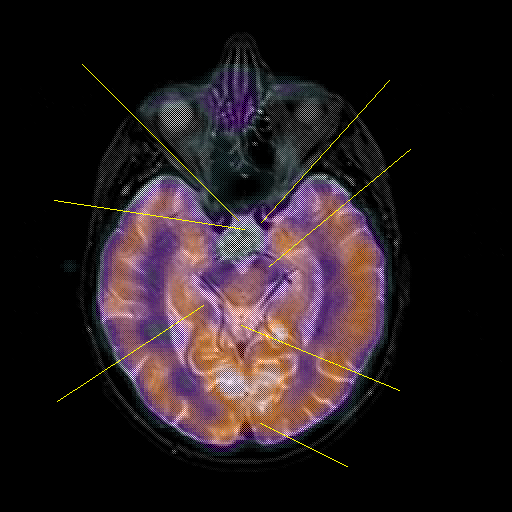

overlay : Slice 22

Slice 22

Pointers

Labeled